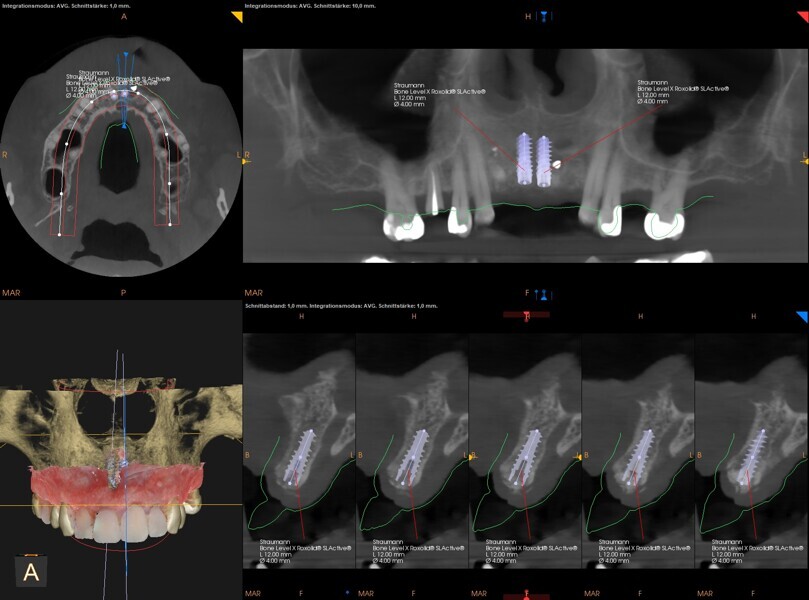

Fig. 9: Implant planning for all four positions.

During the implant planning phase, we created a preliminary plan using 3D imaging software with a prosthetically driven implant planning approach (Figs. 9 & 10), and the plan was exported into surgical guide planning software for final planning and construction of the surgical drilling guide (Figs. 11a–c). The implants were planned in all four positions with the object of identifying the two most optimal and accessible sites for the placement of two implants and the corresponding bridge restoration.

Fig. 10: Final planning for two implants with merged intra-oral scan and CBCT data.